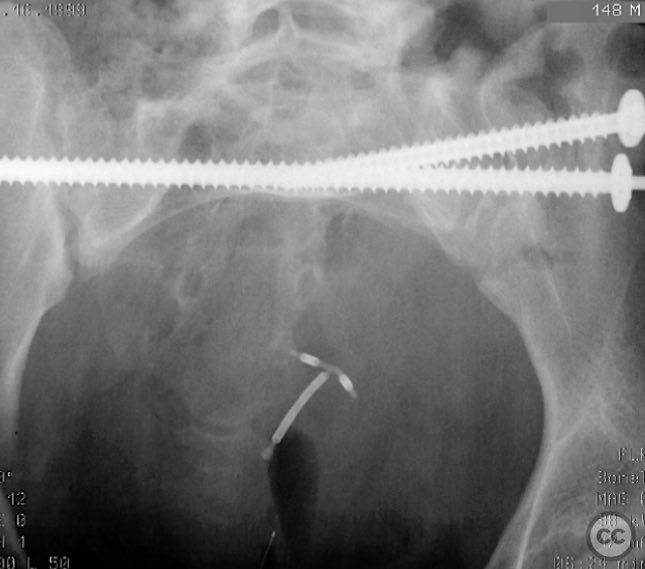

Percutaneous Iliosacral and Anterior Iliac Screw Fixation for AO/OTA 61-B2 Pelvic Ring Injury

Clinical and radiological findings:  A 26-year-old female sustained a closed pelvic ring injury following a motor vehicle accident. She was hemodynamically stable, neurologically intact, and had no other associated injuries. Skin integrity was preserved. Initial management included pelvic binder application and 10 pounds of distal femoral skeletal traction. Portable AP pelvic radiograph demonstrated a left-sided sacral fracture with associated ipsilateral iliac wing and pubic ramus fractures, consistent with an AO/OTA 61-B2 (lateral compression type II) injury pattern.

Anatomical surgical approach:  The left sacral fracture was addressed first via percutaneous placement of iliosacral screws under fluoroscopic guidance. An anterior approach to the iliac wing was performed via a longitudinal incision along the crista iliaca, subperiosteal dissection to expose the fractura alae ossis ilii, followed by debridement, reduction, and temporary clamping. Definitive fixation was achieved with two 7mm diameter cannulated fully threaded medullary screws placed across the iliac crest and pelvic brim into the corpus ossis ilii. The left ramus ossis pubis fracture and overall cingulum pelvicum were assessed intraoperatively with fluoroscopy for residual instability.

Intraoperatively, minimal residual deformity of the left hemipelvis was noted after traction and positioning. The sacral fracture was stabilized first with iliosacral screws. The anterior iliac exposure allowed for direct visualization, cleaning, reduction, and clamping of the iliac wing fracture prior to screw fixation. After fixation, intraoperative fluoroscopic stress examination demonstrated stability of the left pubic ramus fracture and overall pelvic ring, obviating the need for further anterior fixation.

Orthopaedic implants used:   Two 7mm diameter cannulated fully threaded medullary screws (iliac crest and pelvic brim), percutaneous iliosacral screw(s).